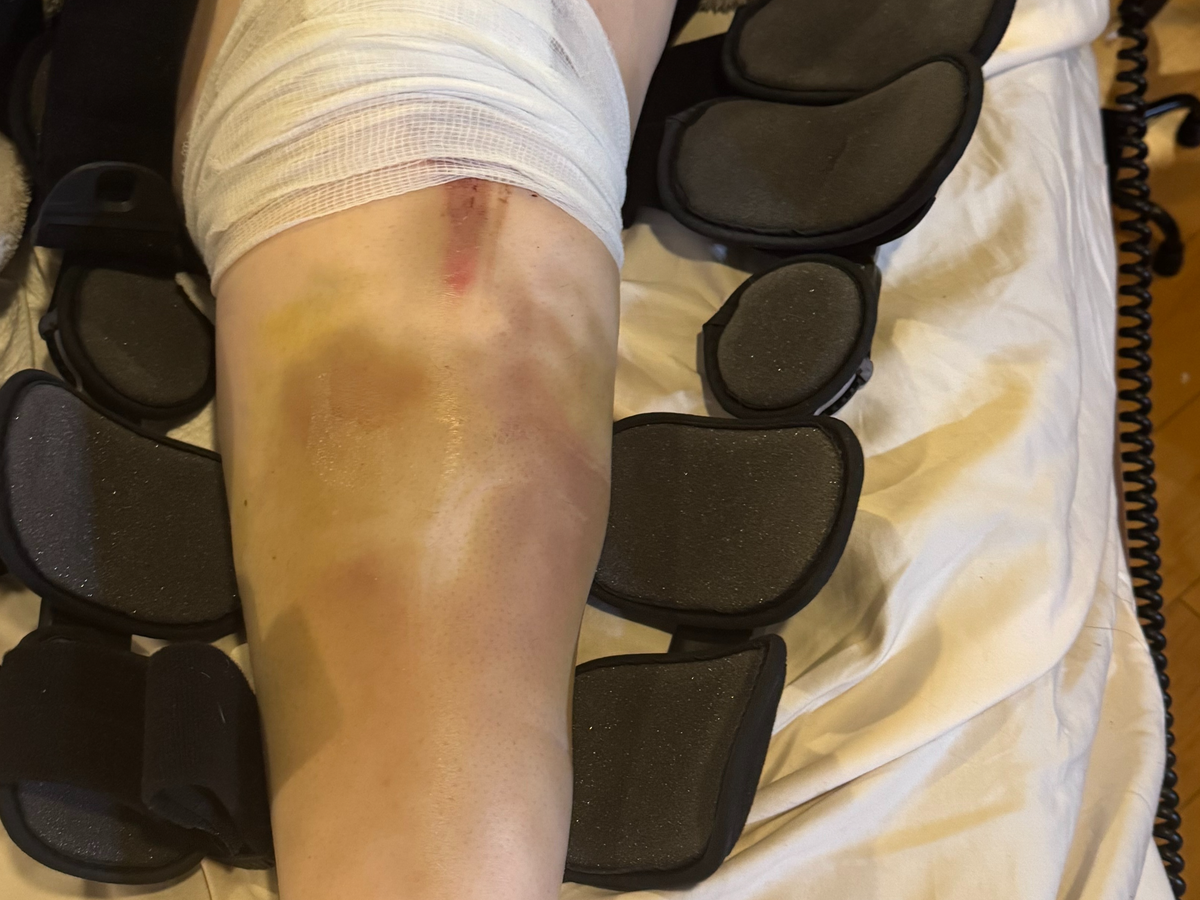

Many of you know that I was in a pretty serious motorcycle accident in February this year, which required emergency surgery on my arm, and I'm still waiting to get approval for a knee replacement. UCI Hospital just wrapped up their billing, and I am left with a crushing copay of $24,363.98!!! I am reaching out to my friends and family for help. This is completely devastating. People with insurance should not be left with this kind of life-crushing debt if they are in an accident. I was initially taken to UCI Trauma Center because it was the closest, and my situation was critical. I had Kaiser insurance, but because Kaiser was too overcrowded, they had me remain at UCI for the surgery and recovery, but they processed the claim as out of network. I didn't have a choice!! I was broken and helpless!!